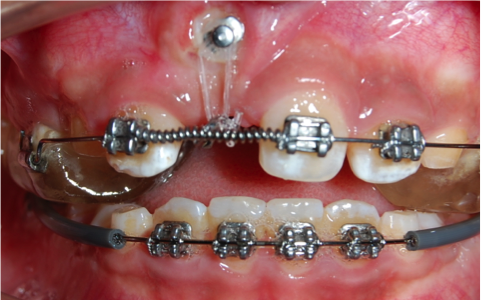

Traccion de un diente retenido